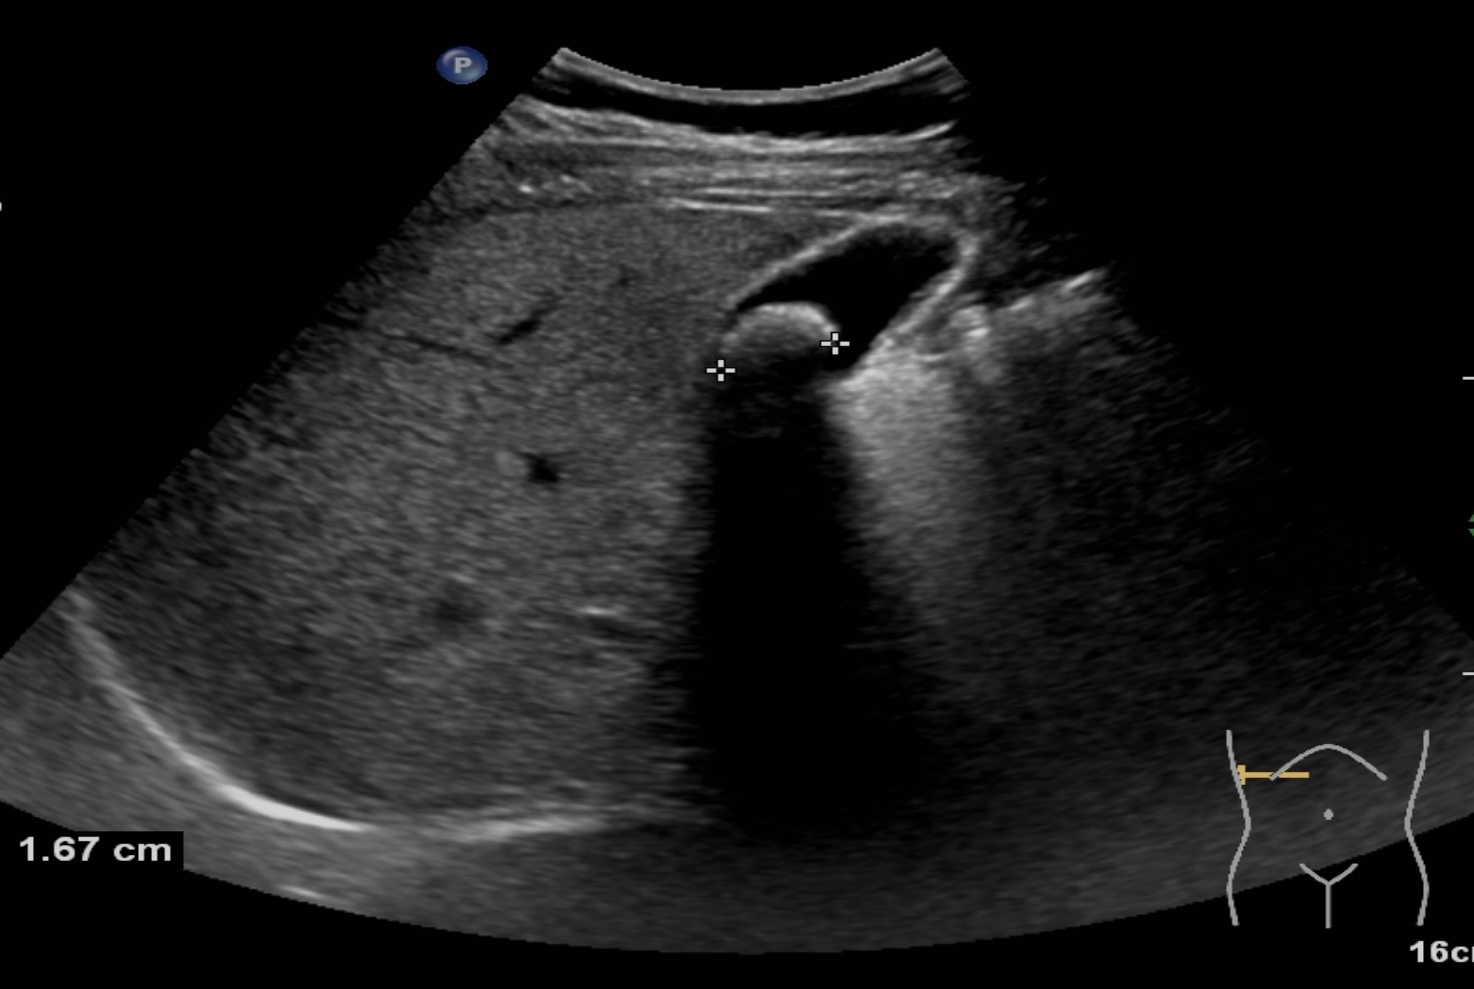

膽結(jié)石診斷方式很多,包括CT、核磁共振膽管造影等方式都可以對(duì)膽結(jié)石進(jìn)行診斷,但是彩超具有無(wú)創(chuàng)、無(wú)、無(wú)輻射、廉價(jià)、快速、可重復(fù)性強(qiáng)等優(yōu)點(diǎn),在臨床上被廣泛應(yīng)用作為膽結(jié)石的首選診斷方式。注意做肝膽彩超檢查必須要空腹,才能準(zhǔn)確檢查出膽結(jié)石哦!

膽囊結(jié)石超聲圖像